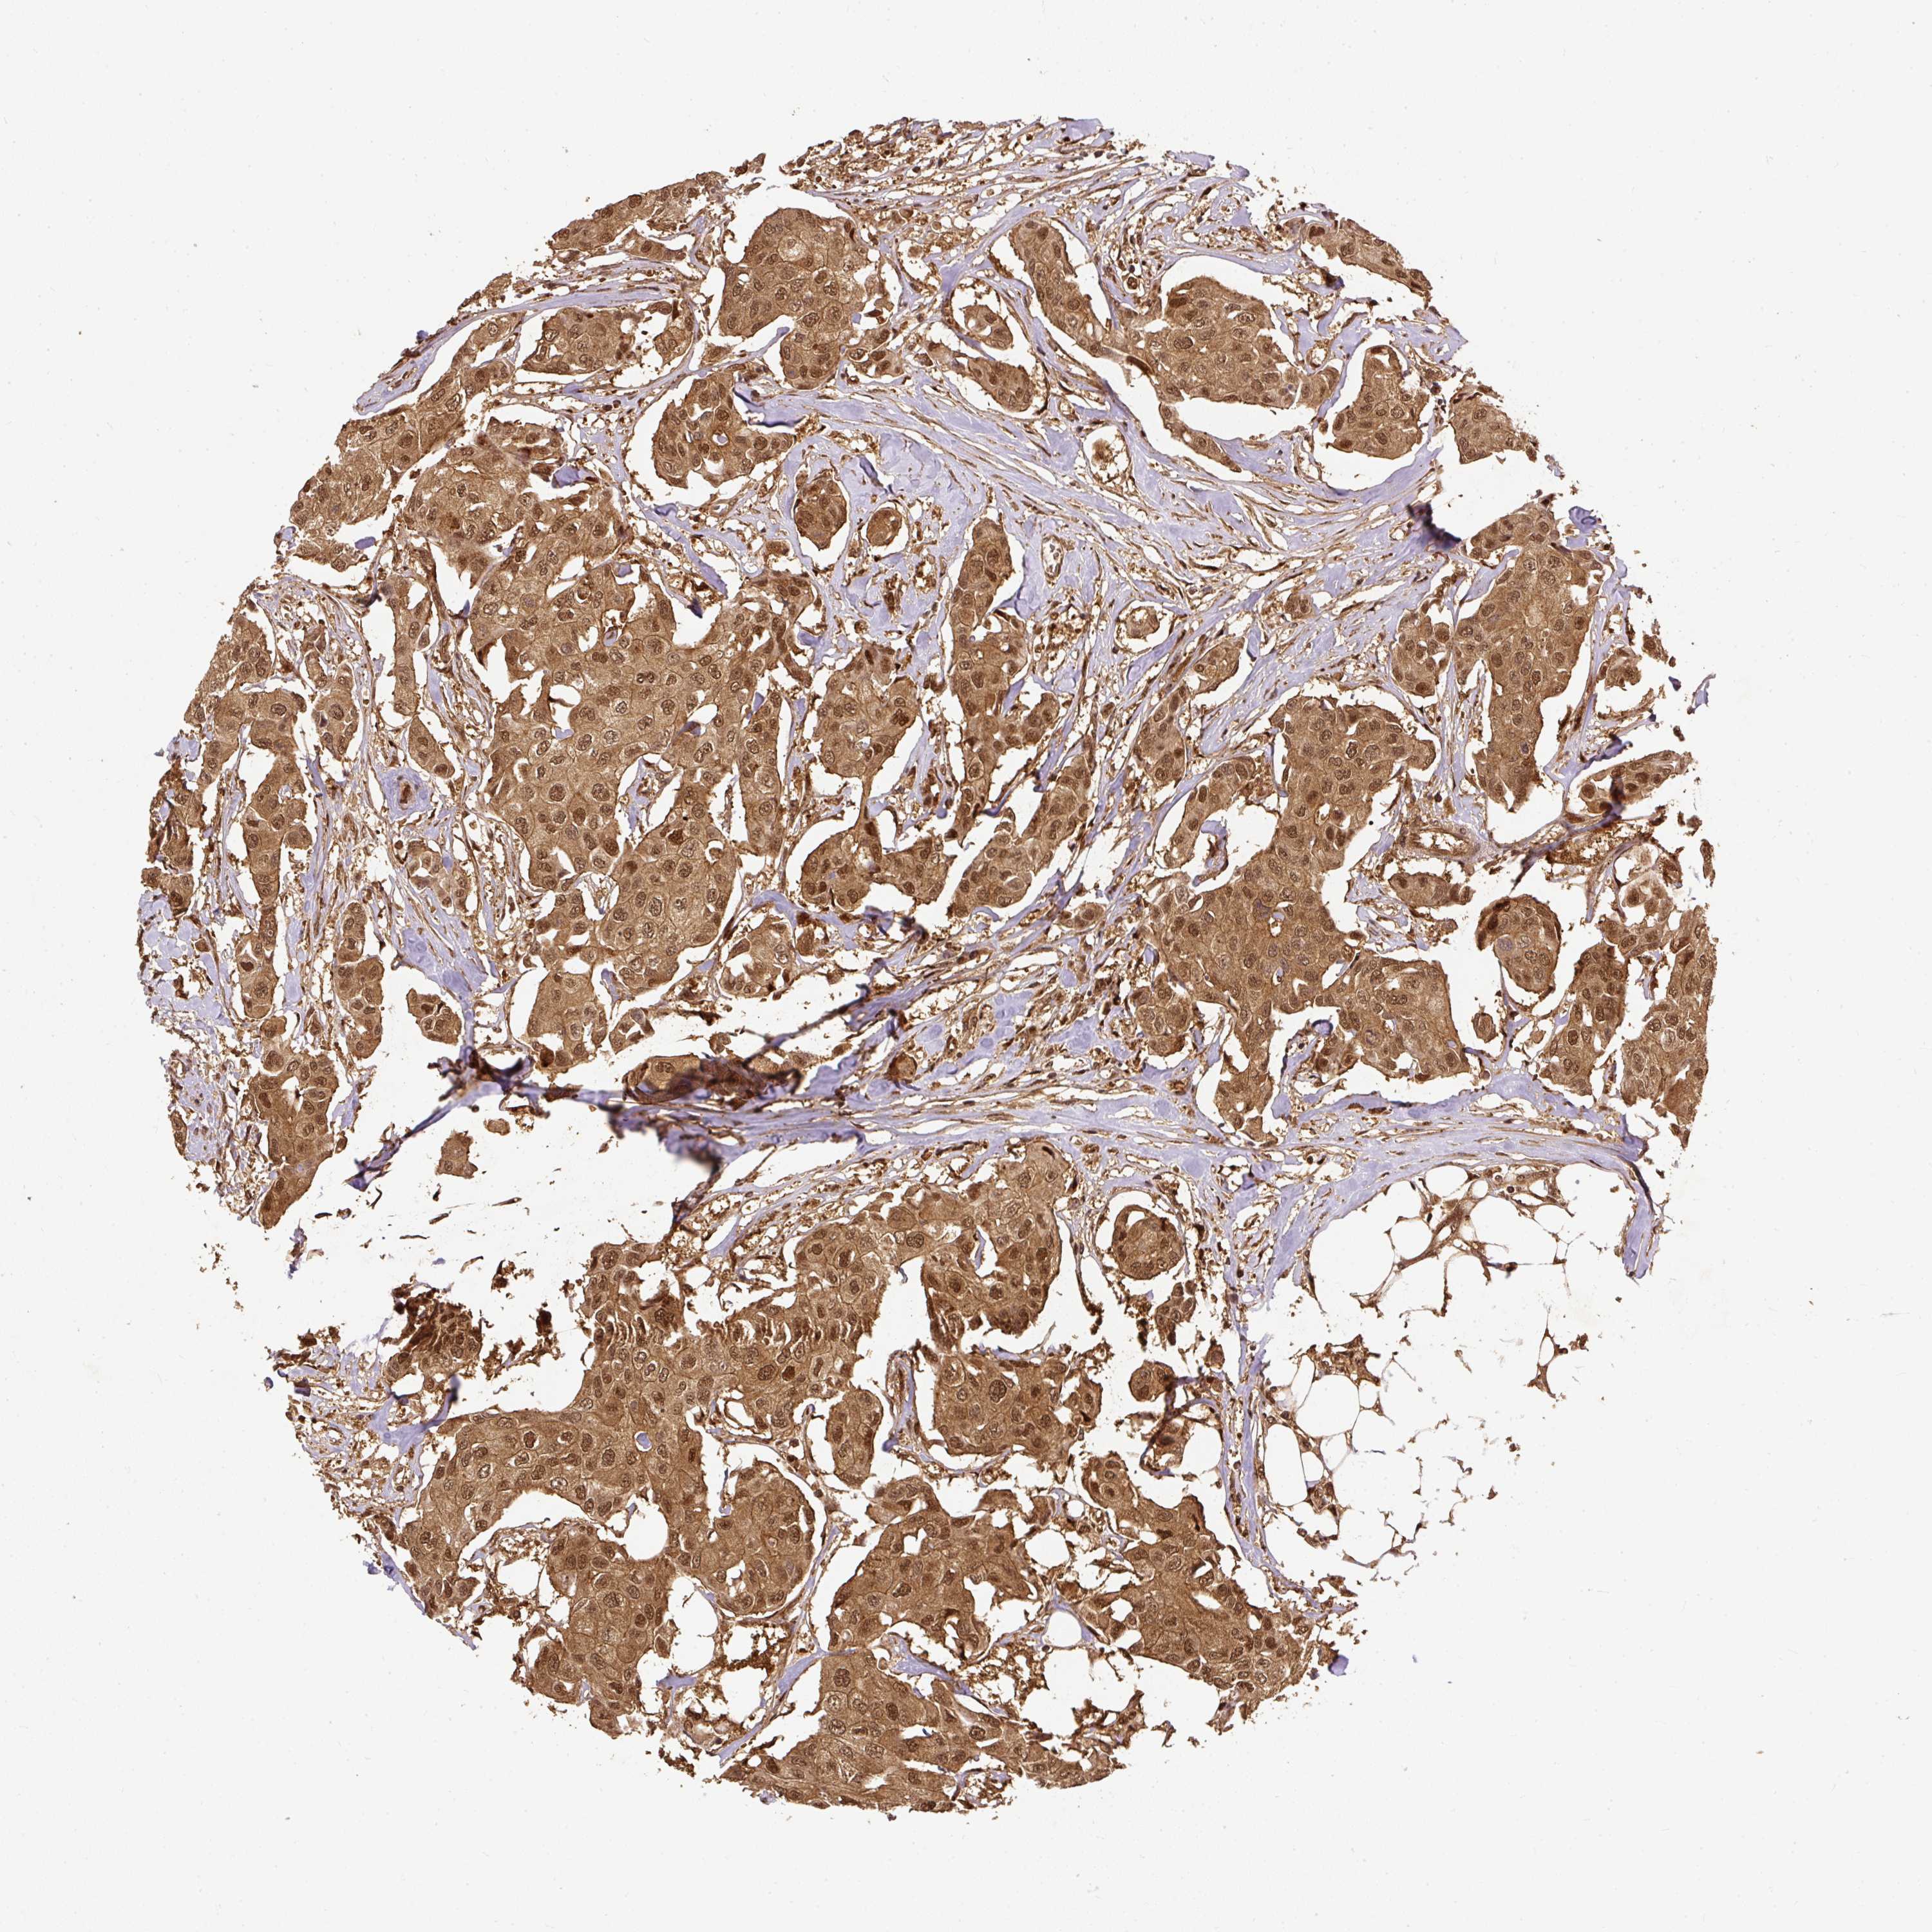

CANCER BREAST CANCER Show tissue menu

BRCA TCGA BRCA VALIDATION PROTEIN EXPRESSION